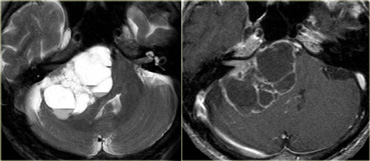

On the left some examples of tumors with a low signal intensity on T2WI.

1. Melanoma metastases have a low SI on T2WI as a result of the melanin.

2. GBM can have a low SI on T2WI because sometimes they have a high nuclear-cytoplasmic ratio. Most GBM's, however, are hyperintense on T2WI.

3. PNET typically has a high nuclear-cytoplasmic ratio. PNET is mostly located in the region of the 4th ventricle, but another, less common, location is in the region of the pineal gland.

4. Mucinous metastases can have a low SI on T2WI because they often contain calcifications..

5. Meningiomas are mostly of intermediate signal.

They can have a high SI on T2WI if they contain a lot of water.

They can have a low SI on T2WI if they are very dense and hypercellular or when they contain calcifications.